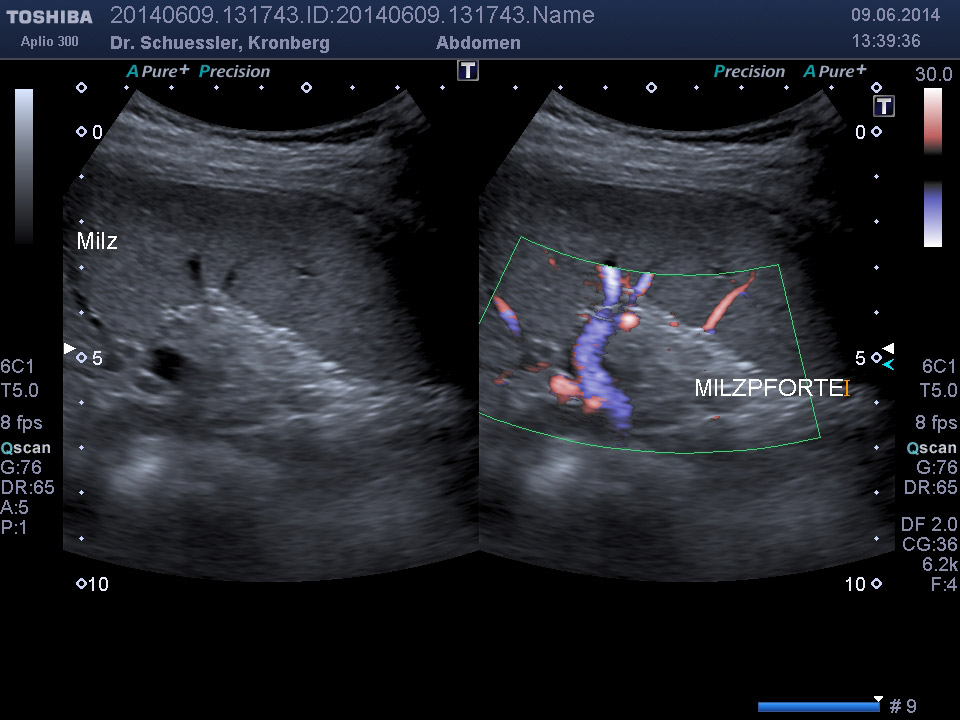

Die Bauchultraschalluntersuchung ist das wichtigste Verfahren zur Beurteilung der gesamten Bauchorgane. Sämtliche Bauchorgane sind dem Ultraschallverfahren ohne Belastung für den Patienten gut zugängig.

Durch Ergänzung des farbkodierten Duplexverfahrens läßt sich die Durchblutungssituation der Bauchorgane erfassen.